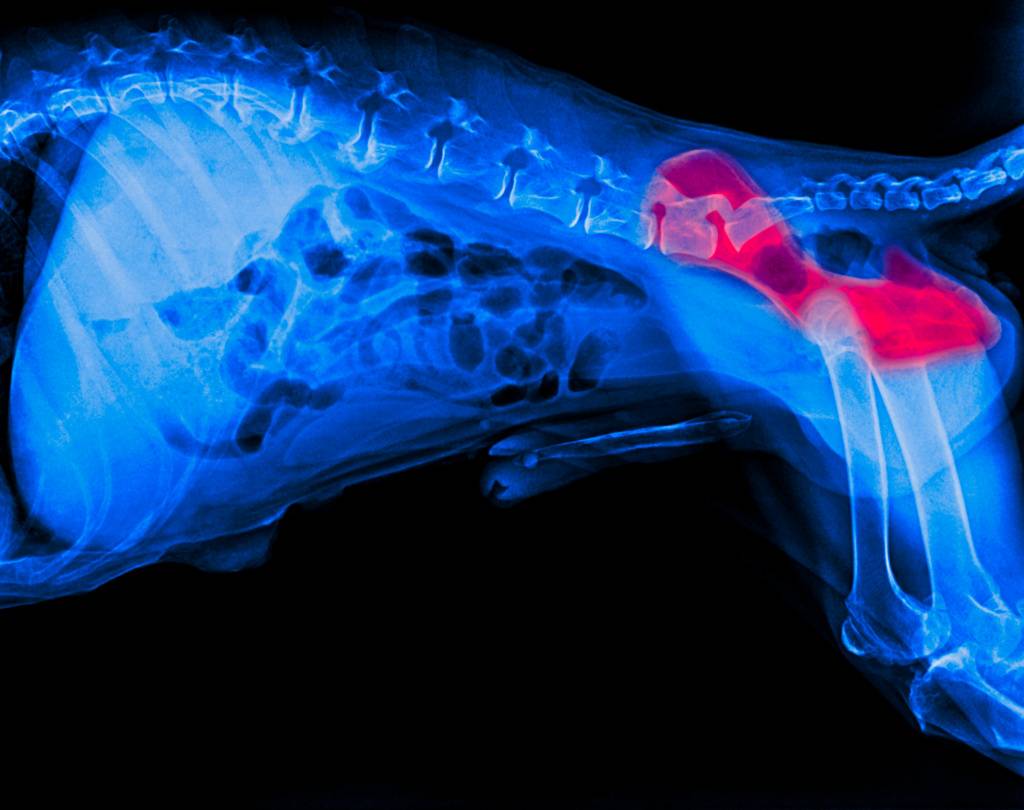

В норме (у здорового животного) головка бедренной кости идеально подходит к впадинке на тазовой, они плотно соприкасаются друг с дружкой. При дисплазии же у пса отмечается наличие зазора (пустого пространства) между головкой и впадиной. При движении происходит трение, как результат, суставные поверхности стираются и разрушаются.

Распознать симптомы дисплазии не так уж и сложно, однако диагноз подтвердиться может только после проведенных дополнительных исследований. Наиболее результативным является рентген. На снимке будет заметен зазор между суставными поверхностями костей или же уже начавшаяся дегенерация. Однако есть и видимые клинические признаки, которые владелец может заметить и без рентгена.

Для диагностики используют рентген, а также ручной осмотр больных конечностей. На ранних стадиях для определения дисплазии у собак применяют тест Ортолани. Тест обычно проводят под анестезией, поскольку мышечное напряжение мешает диагностике. Врач производит определенные манипуляции с конечностями, что позволяет определить, есть ли подвывих и дисплазия ТБС.

Рентген — наиболее надежный способ диагностирования дисплазии